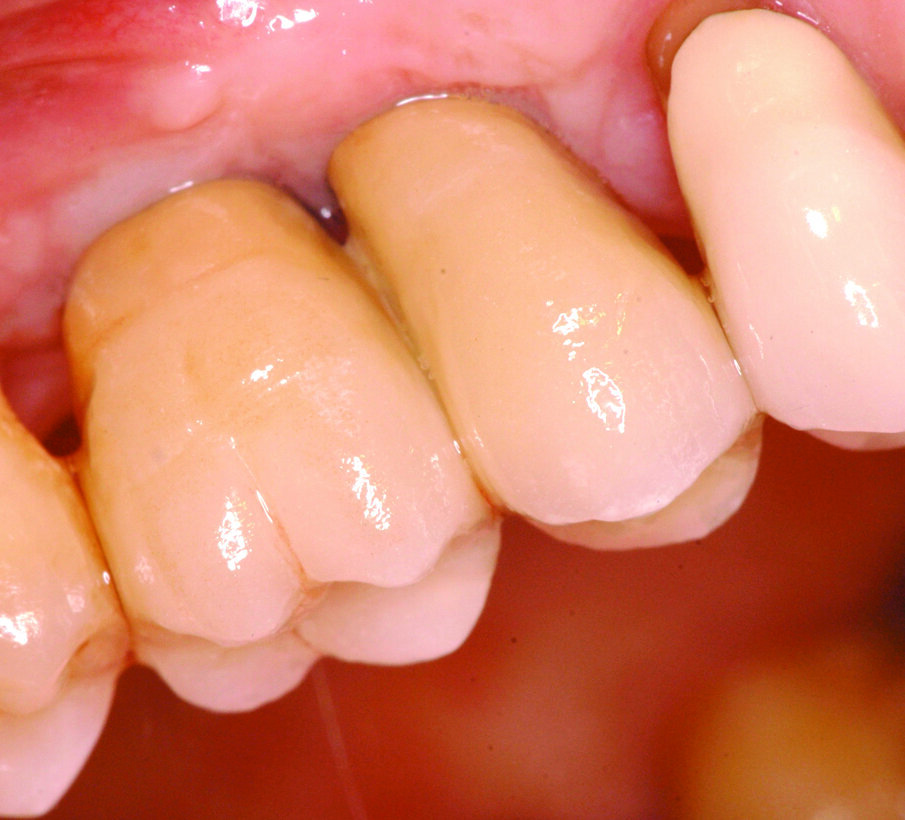

Una volta eseguito il disegno dell’antrostomia (Fig. 5), si procede al sollevamento della membrana con tecnica manuale (Figg. 6, 7) e all’iniziale inserimento di biomateriale granulare 0,5-1 mm (AlphaBio’s Graft, Alpha-Bio Tec, Israele). La corticale viene lasciata integra e aderente alla mucosa schneideriana in modo da diventare il futuro pavimento dell’antro (Fig. 8), anche per supportare il collasso della membrana durante il periodo di guarigione. A protezione della stessa è inserita una spugnetta di collagene equino (Condress, Smith&Nephew, UK). Contestualmente si procede con l’inserimento di due impianti autofilettanti SPI 3.75 x 13 mm (Alpha-Bio Tec, Israele) (Figg. 9, 10) e, al termine, viene ultimato il riempimento con biomateriale (Fig. 11). L’antrostomia viene poi coperta con una membrana riassorbibile 15 x 20 (AlphaBio’s Graft, Alpha-Bio Tec, Israele) e il lembo viene passivato e suturato con due linee di sutura 5-0: una a materassaio orizzontale e l’altra con punti staccati (Vicryl, Ethicon, USA) (Fig. 12). La paziente viene dimessa con la seguente terapia farmacologica: amoxicillina cpr 1 gr (1 cpr ogni 12h per 6 giorni), Prednisone cpr 25 mg (2 cpr per due giorni a scalare) per il controllo dell’edema post-operatorio e sciacqui con clorexidina 0.2% dal giorno successivo (1 sciacquo al giorno per 15 gg). Le suture sono rimosse a 15 giorni e la paziente è inserita in un programma di recall a cinque settimane per gestire eventuali complicanze durante la maturazione dell’innesto. Viene eseguito il secondo tempo chirurgico dopo 6 mesi e, verificata l’avvenuta osteointegrazione degli impianti, vengono rilevate le impronte e il caso è finalizzato con due corone unite in metallo ceramica (Figg. 13-15). Al termine della riabilitazione, visto il buon mantenimento igienico, la paziente viene inserita in un programma di follow-up a sei mesi (Figg. 16, 17).

Figg. 13-15_Particolari dei monconi in titanio e delle corone in metallo ceramica.